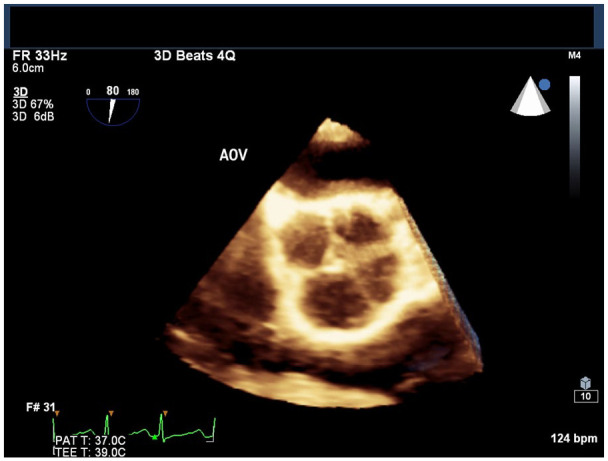

We describe a 30-year-old Caribbean-Black woman with a clinical presentation suggestive of a transient ischemic attack (TIA) with no conventional cerebrovascular risk factors, albeit with a newly diagnosed quadricuspid aortic valve (QAV) with moderate aortic regurgitation (AR). Although QAV is a recognized congenital cardiac defect, its association with TIA remains elusive. This case highlights the importance of considering potential atypical etiologies, such as QAV, in the evaluation and management of young patients presenting with cerebrovascular events.

Abstract Image